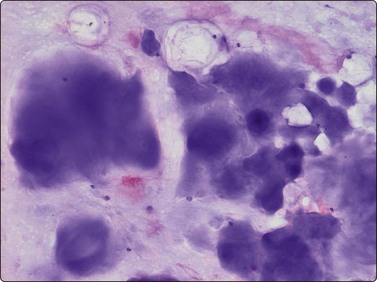

The characteristic findings are the abundant background of myxoid ground substance and the large, physaliphorous cells with abundant pale, vacuolated, bubbly cytoplasm and well-defined cell borders. The myxoid matrix, often fibrillar, intensely purple in MGG smears, pale pink in H&E, forms a network encircling individual tumor cells, cell clusters or fragments (Fig. 16.28). The physaliphorous cells have one, sometimes two, rounded nuclei of moderate size, a bland chromatin and small nucleoli. Moderate anisokaryosis is common (Fig. 16.29A). Some tumors show clusters of markedly pleomorphic cells with prominent nucleoli, and multinucleated tumor giant cells may be present (Fig. 16.29B). There are also clusters of small to medium-sized, non-characteristic or epithelial-like cells with rounded nuclei. The cytoplasm of these cells may be vacuolated; some cells have one large vacuole pushing the nucleus to the periphery and may resemble signet ring cells (Fig. 16.30A). The main differential diagnosis is chondrosarcoma. If only wet-fixed smears are available, metastatic clear cell carcinoma, especially renal cell carcinoma or mucus-producing adenocarcinoma can also cause differential diagnostic difficulties. The abundant ground substance may be inconspicuous in H&E or Pap smears and the epithelial-like tumor cells may give a false impression of an epithelial neoplasm (Fig. 16.30B). Typical physaliphorous cells are never encountered in chondrosarcoma and the network of myxoid matrix encircling individual cells is not a feature of either chondrosarcoma or metastatic carcinoma. A chordoma originating in the cervical spine does not always present as a midline tumor and, if information on the radiologic finding is not available, may be interpreted as a malignant myxoid soft tissue tumor. Chordomas typically express S-100 protein and low molecular weight cytokeratins. The cytological appearance of chordoma in FNB has been evaluated in rather large series.37-39

image image

Fig. 16.30 Chordoma

(A) Some cells in chordomas may have one large vacuole pushing the nucleus to the periphery and may resemble signet ring cells (H&E, IP); (B) In H&E or Pap smears the epithelial-like tumor cells may give a false impression of an epithelial neoplasm (H&E, LP).